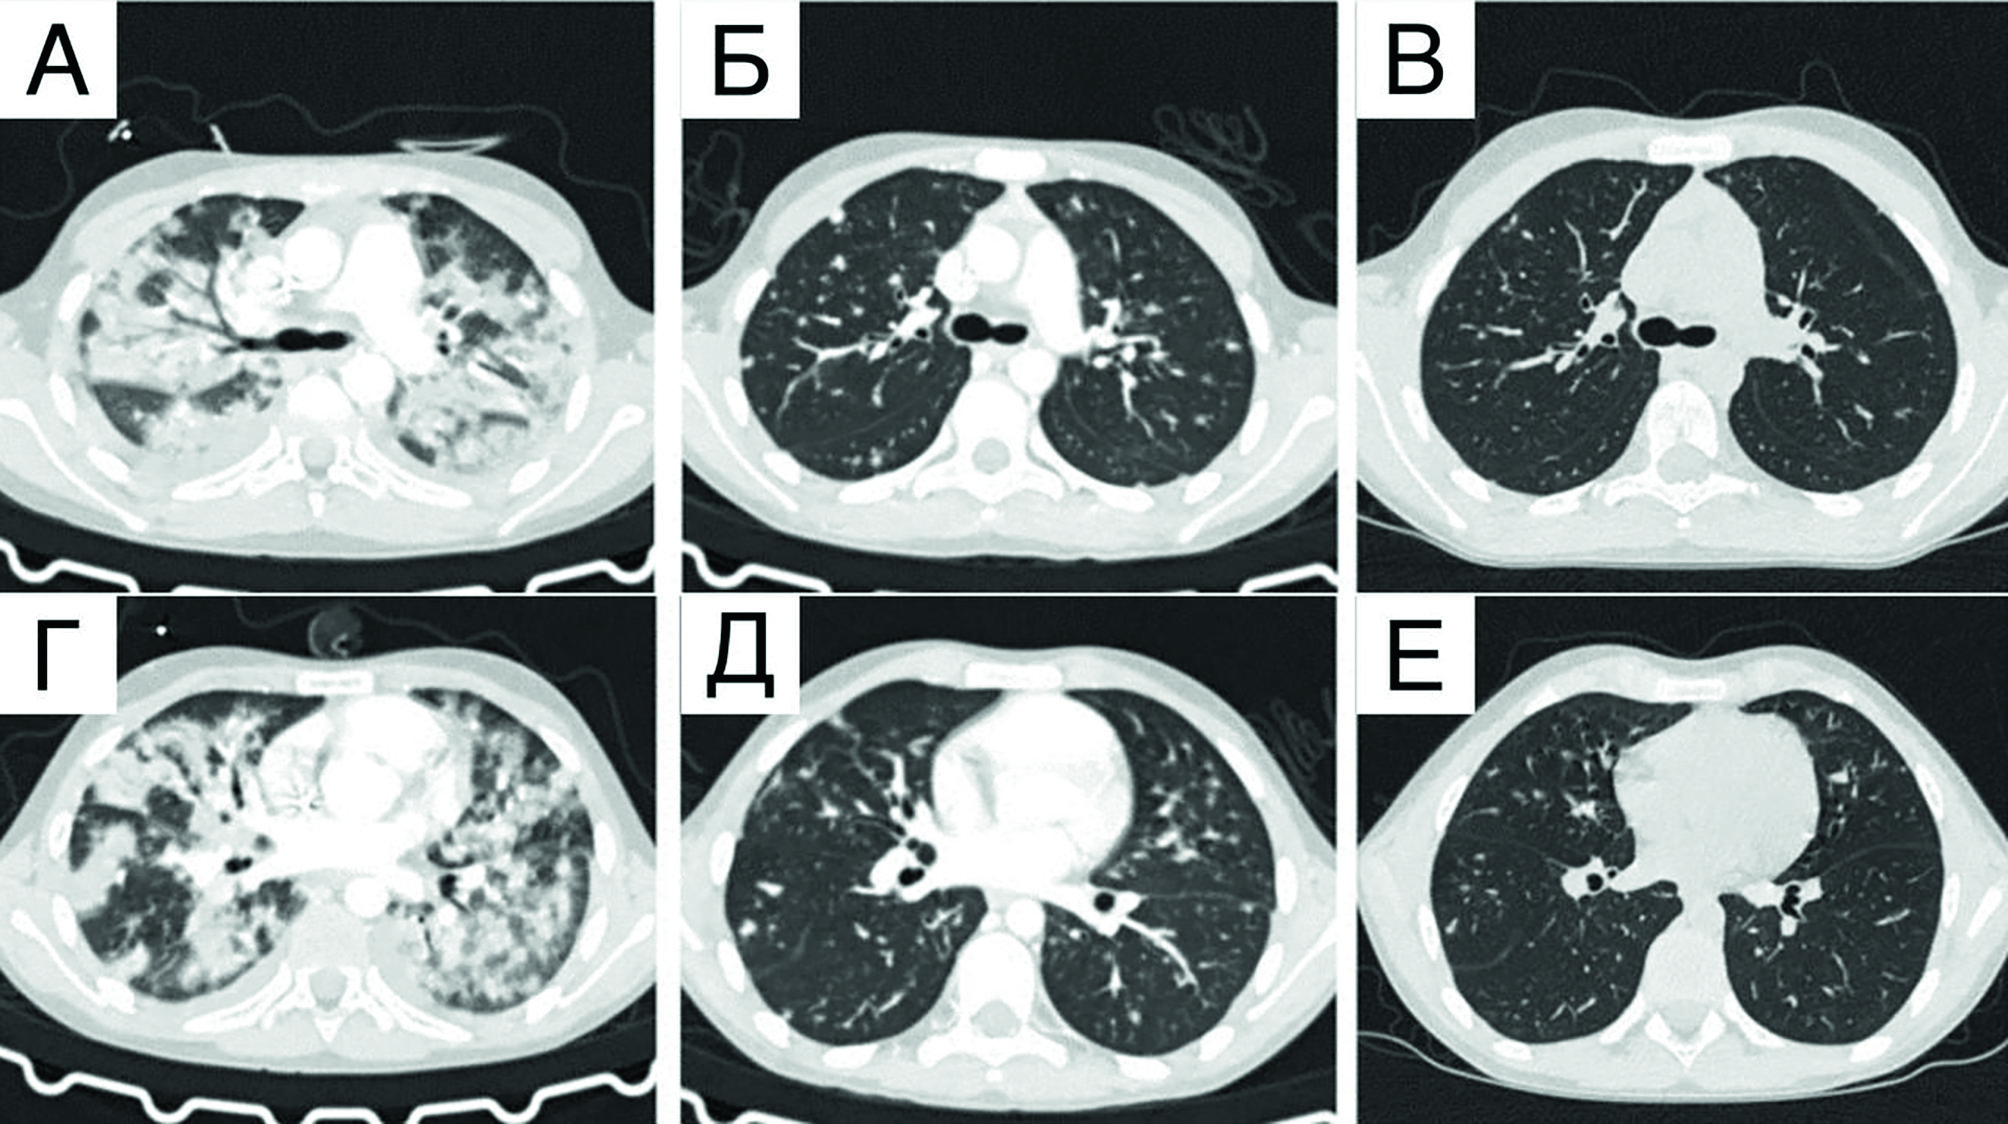

Рисунок 3. КТ органов грудной клетки с контрастным усилением до начала специфической терапии (аксиальная проекция): А, В - появление многочисленных очагов в обоих легких; Б, Г - отрицательная динамика за 7 дней от предыдущего исследования в виде увеличения очагов с формированием массивных инфильтраций

Figure 3. Contrast-enhanced chest CT scans done before the start of specific therapy (axial view): A, B - multiple lesions in both lungs; Б, Г - progression over 7 days following the previous CT exam: enlarged lesions and extensive infiltrates